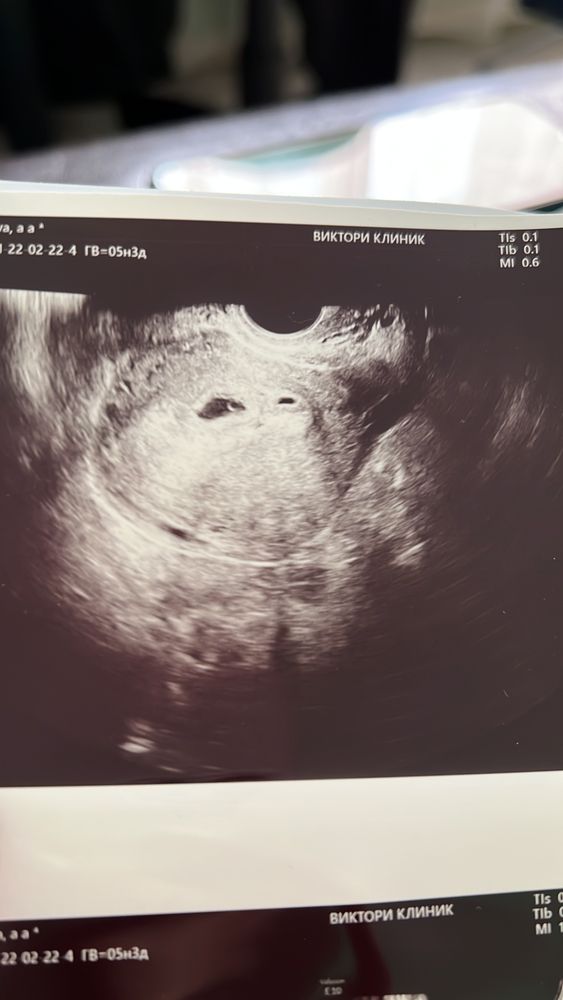

21дпп и наше первое УЗИ

Класс! Я искренне Вас поздравляю! Какая красивая фотография, ваши эмоции и радость аж телефон заставила ярче гореть))))))Желаю в нужный срок стать мамочкой двух крошек! начихайте пожалуйста на меня, сильно, сильно!🙏

Поздравляю вас! Лёгкой беременности))) красота какая на фото)

🥰🥰🥰идеальная первая фотография)) поздравляю🎉🎊🎉🎊🎉🎊 растите и пусть беременность будет лёгкой 💫